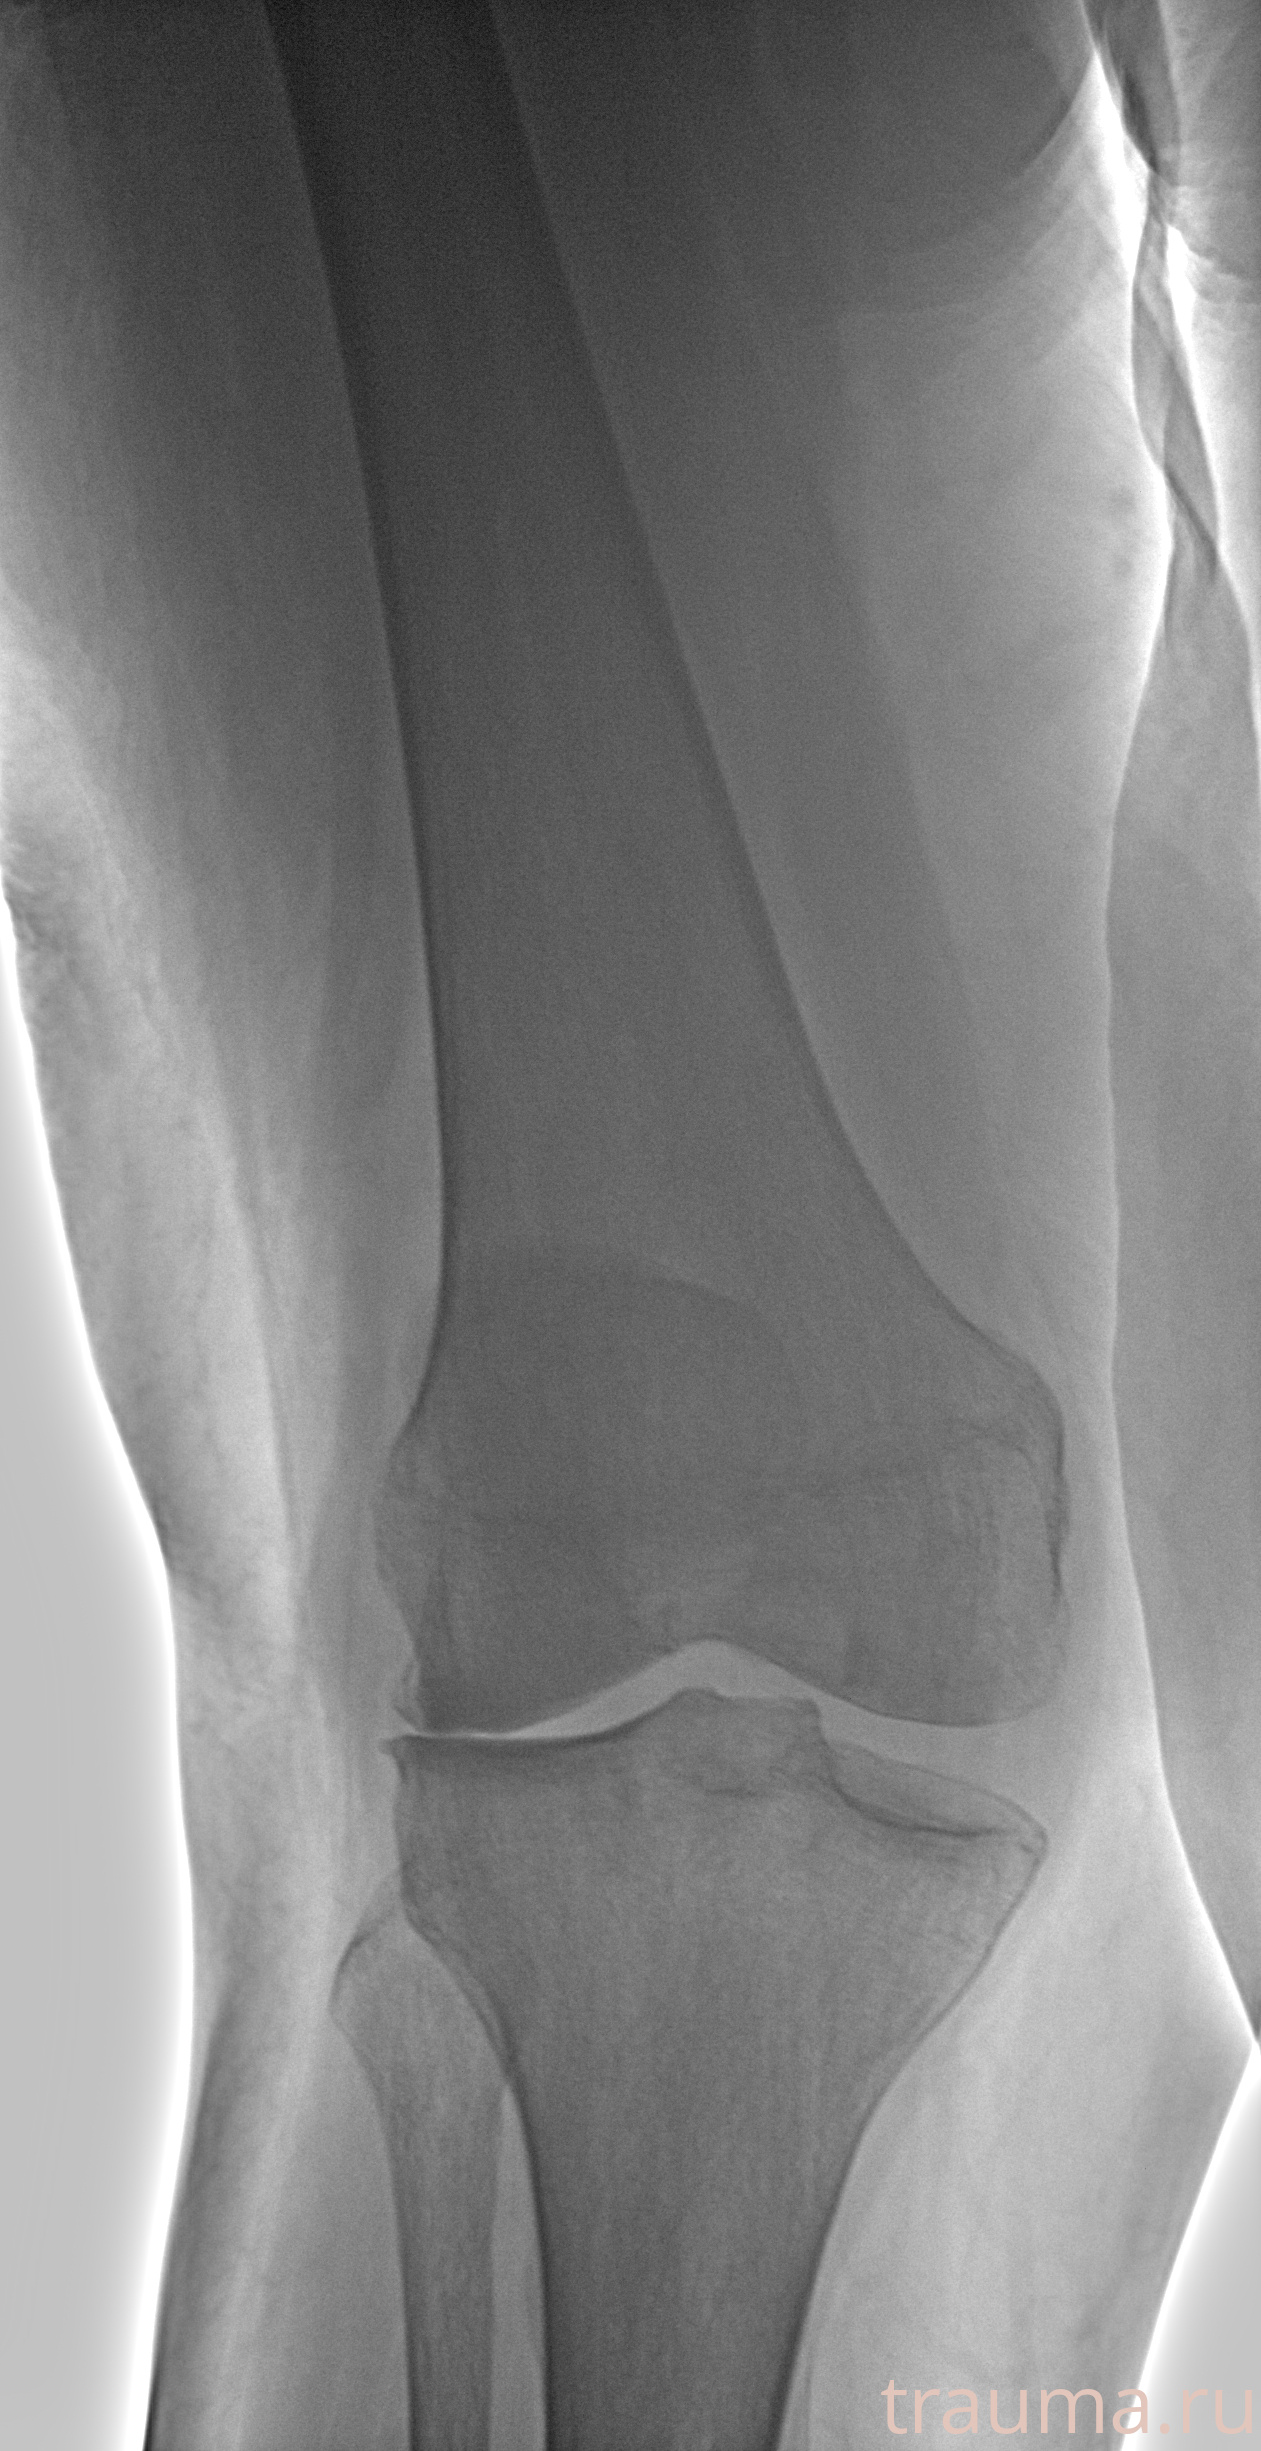

Левая

Рентгенограммы

Рентген на дому: по вашему адресу приезжает врач-рентгенолог, травматолог-ортопед с мобильным рентгеновским аппаратом, проводит диагностику травмы или заболевания, делает необходимые рентгенограммы, дает рекомендации по дальнейшему лечению. Получить качественные снимки в домашних условиях возможно благодаря уникальной методике, разработанной МосРентген Центром для института  Склифосовского